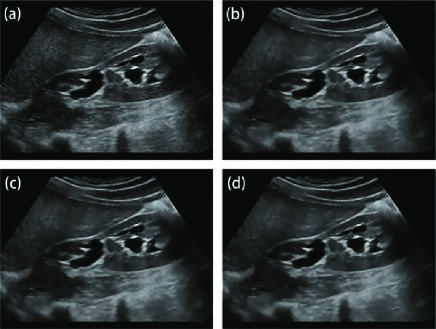

where and are the pixel intensities of pixel in the noise-free image and the synthesized noisy image respectively, and is a zero-mean Gaussian noise with variance . We applied this noise model to Fig. 3(a), which consists of smooth regions and various local features. Three levels of noise were tested by setting . Fig. 3(b) depicts the synthetic image with noise variance .

Fig. 3 depicts the denoised images of different filters with their optimal parameters. The Frost filter has clear features, but it retains a significant level of noise. The SRAD remove noise better but produces smoother edges and removes some low-contrast features compared with Frost. Though OBNLM and NLLRF have good performance in high-contrast features, they cause some meaningful low-contrast features to become indiscernible after noise removal. Both SBF and ADLG produce fuzzy boundaries, and ADLG removes considerable details. Therefore, the PFDTV method achieves the best performances in noise removal and feature preservation.